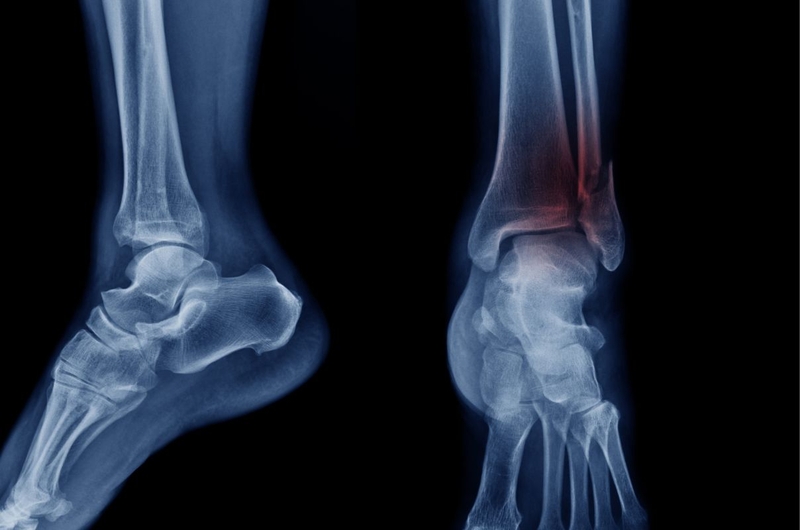

Khớp cổ chân được tạo thành bởi 3 xương gồm: Xương mác, xương chày và xương sên. Các xương đó được cố định với nhau bằng hệ thống dây chằng chắc chắn. Các cơ, gân, dây chằng bao quanh xương giúp chân, đặc biệt là bàn chân có thể cử động uyển chuyển, linh hoạt. Xương cổ chân nâng đỡ trọng lượng cơ thể và hỗ trợ hoạt động của các xương xung quanh.

Chấn thương cổ chân là các tổn thương xảy ra ở vùng cổ chân như: Trật khớp, gãy xương, nứt vỡ xương, tổn thương gân, tổn thương dây chằng. Các tổn thương có thể xảy ra trong khi chúng ta chơi thể thao, tham gia giao thông, lao động, trượt ngã trong sinh hoạt hàng ngày,… Theo thống kê, có khoảng hơn 50% trường hợp chấn thương ở cổ chân xảy ra do té ngã, va chạm khi chơi thể thao. Các chấn thương này có thể xảy ra với bất cứ ai trong chúng ta nhưng phổ biến nhất là nam giới 25 - 24 tuổi.

Trường hợp gãy xương cổ chân và bong gân thường có biểu hiện khá giống nhau và dễ gây nhầm lẫn. Do đó, người bệnh cần đi khám và được chẩn đoán chính xác tình trạng bằng các kỹ thuật chẩn đoán hình ảnh. Các triệu chứng thường gặp nhất khi cổ chân bị chấn thương như:

Khi người bị chấn thương cổ chân đi khám, bác sĩ sẽ hỏi về tình huống gây chấn thương, đánh giá mức độ sưng đau, bầm tím. Sau đó, có thể bác sĩ sẽ chỉ định chụp X quang cổ chân, chụp cộng hưởng từ hay cắt lớp CT tùy trường hợp. Căn cứ vào tình trạng thực tế của từng bệnh nhân, bác sĩ sẽ chỉ định cách điều trị khác nhau. Tuy nhiên, các phương pháp điều trị phổ biến nhất thường là: